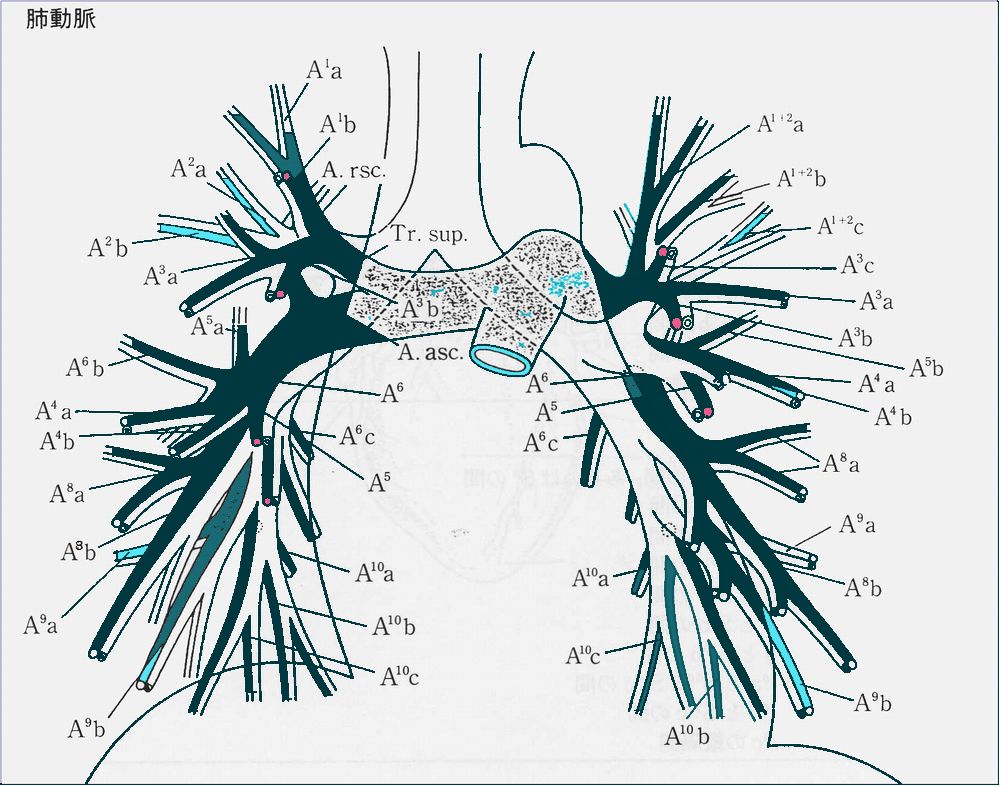

内側展開図(下図) 背面(下図)(背中側から見ている) 体表からみた肺区域 レントゲン写真に投影する肺区域 レントゲン側面像(展開像:魚の開きのイメージ) 肺・気管支のイメージ 気管支の分枝 肺の血管走行 肺門部のリンパ節 A-P window 大動脈と肺動脈の交差する部位、リンパ節腫大の目印になります。 肺野の区分 肺野を便宜的に3等分して肺野での位置を表示するために使用します。 縦隔陰影・心陰影 正常の胸部レントゲン写真像:チェックポイント 1.気管支B3bの断面とその内側の肺動脈A3bとB6(左)は必ず確認。

2.右気管支は25゜の角度で分枝し太くて短い、左は35゜程度で細くて長い。

3.左の肺動脈の肺門部での位置は右のそれより1.5cm程高い。

6.肺動脈A8-10の走行とその分枝まで見る癖をつけること。